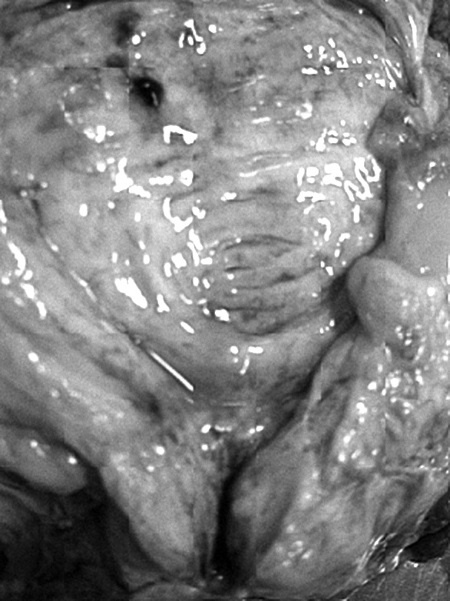

Атеросклероз сосудов головного мозга. Отек головного мозга